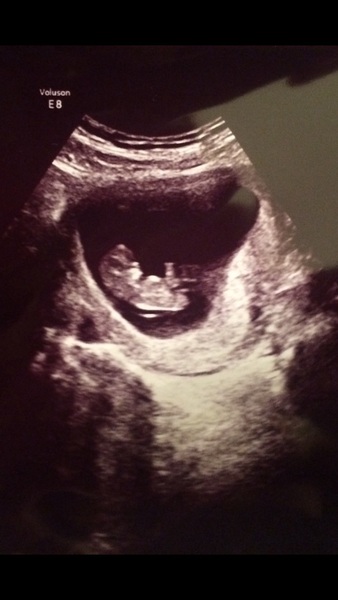

lucieloos · 27/10/2016 19:11

Here's the one causing all the trouble! I can't believe how much it has changed since our last scan at 7w5d it looks like a proper baby now!

Oh that's great lucie! It does look like a proper baby.